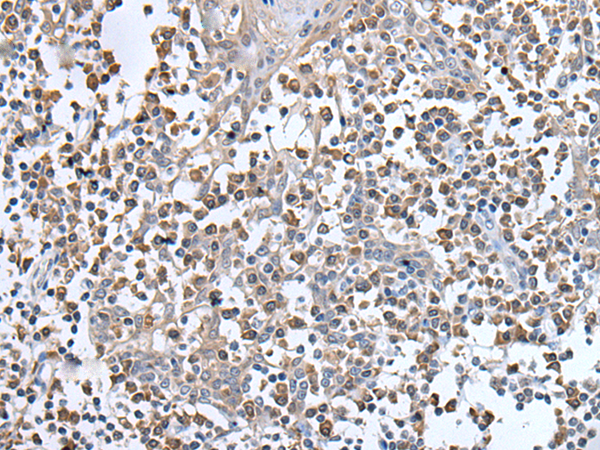

分类: 科研抗体货号: P12879别名: RECQ3; RECQL2; RECQL3应用: IHC反应种属: Human